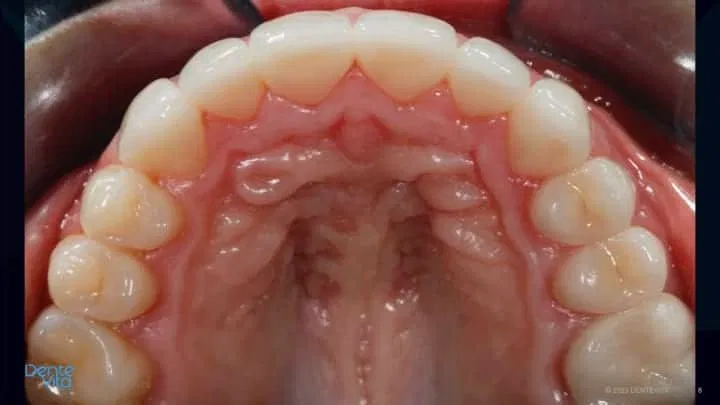

One option to reverse tooth drift is by utilizing pre-orthodontic treatment solutions to intrude/translate affected teeth, thereby re-establishing correct tooth position, gum-line positions, and re-capture vertical/horizontal restorative space for future teeth rehabilitation/restoration.

After completion of successful orthodontic therapy, missing tooth structure was rehabilitated/restored with conservative 360 degree and three-quarter porcelain veneer therapy, along with posterior occlusal partial coverage onlay restorations.